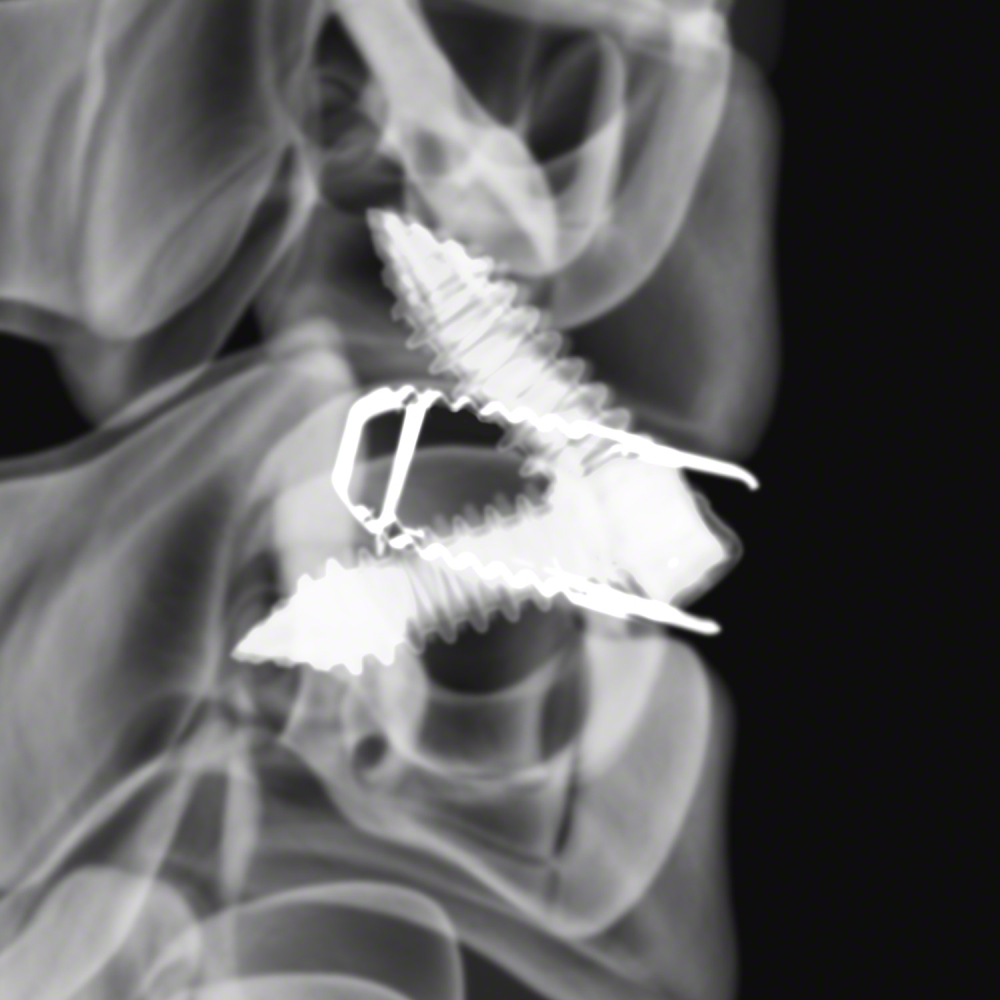

The ArcadiusXP C® Spinal System is intended to be used as an interbody fusion cage as a stand-alone system with two bone screws. It is inserted between the vertebral bodies into the disc space from C2-C3 to C7-T1 in skeletally mature patients.

- Two titanium markers for X-ray verification

- Diverging screw design

- 35° cranial-caudal orientation

- Dual locking mechanism